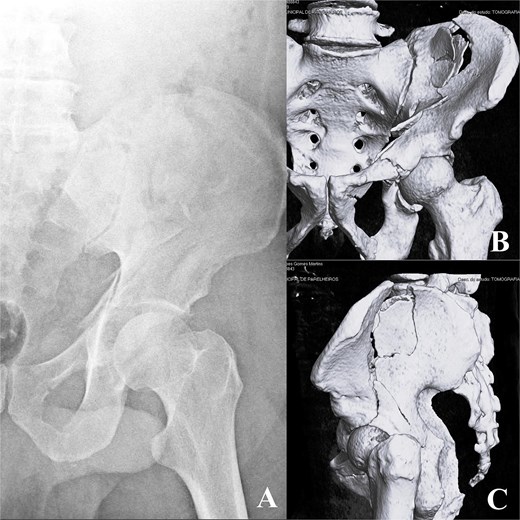

A 58-year-old male presented following a 3-meter fall, with an isolated ABC acetabular fracture of the right side (Fig. 1). Surgery was performed 2 days after the injury using an anterior pelvic approach via the Pfannenstiel incision combined with the first window of the ilioinguinal approach. Fixation began with the iliac crest using 4.5 mm cannulated screws to anchor the constant fragment, followed by a calcaneal plate to address comminution of the iliac wing, and a reconstruction plate for the anterior column (Fig. 2). As the posterior components were well-aligned post-fixation, a posterior approach was deemed unnecessary. Post-operative after 24 months radiographs and TC demonstrated anatomical reduction with no signs of implant failure (Fig. 3), just as shown in the TC comparison (Fig. 4). The physical exam presents a satisfactory range of motion (Fig. 5). Pain, function and quality of life outcomes were assessed using the Visual Analog Scale (VAS), Majeed Pelvic Score, and SF-12 up to 24 months post-operatively, respectively. The results are summarized in the following table (Table 1) and graphic (Fig. 6).

Pre-operative radiograph (A) and computed tomography (CT) scan (B, C).